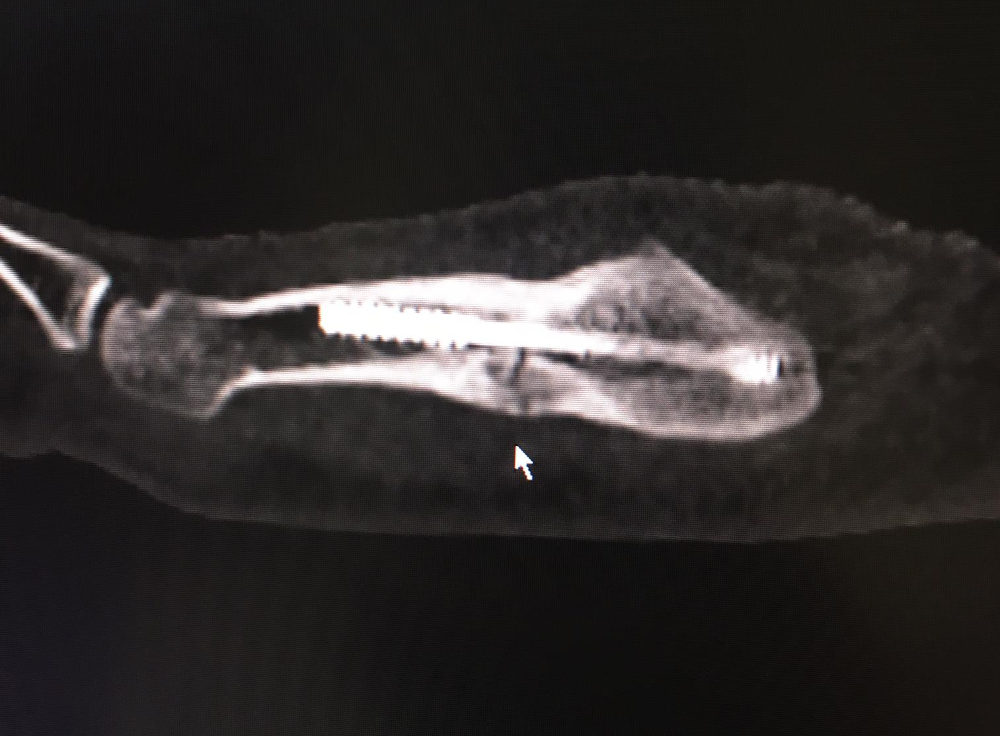

La fracture est clairement visible sur la radiographie

Six semaines plus tard, je reprends l’entraînement. Après ma première séance avec Wacker Thun, je ressens des douleurs au pied, mais je pars quelques jours plus tard au rassemblement de l’équipe nationale en espérant que cela ira quand même. Comme les douleurs persistent, je les mets sur le compte de mon activité accrue et compte simplement interrompre l’entraînement collectif pour quelques jours. Alors que j’accompagne chez le médecin un coéquipier de l’équipe nationale qui s’est foulé le pied, je décide d’en avoir le cœur net et passe moi aussi une tomographie. « M*** ! Ça va être chaud pour les Championnats d’Europe », me dis-je lorsque le médecin m’annonce que mon pied est de nouveau cassé. Une nouvelle opération n’est pas envisageable, car elle sonnerait le glas de mes rêves de Championnats d’Europe.